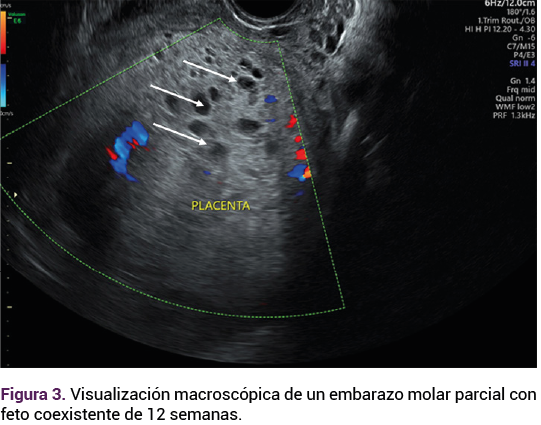

El ultrasonido pélvico transvaginal evidenció la existencia de un feto vivo de 12.6 semanas, por longitud cráneo-caudal (Figura 1), con discordancia de cavidades cardiacas ventriculares, comunicación intraventricular, ductus venoso patológico con onda invertida, translucencia nucal de 1.5 mm; placenta oclusiva total, con múltiples quistes en todo su espesor de 26 mm y vesículas a nivel placentario (imagen en “panal de abeja”) que corresponden a las vellosidades coriónicas marcadamente hidrópicas. Figura 2

<strong>Figura 1</strong>

Figura 1.